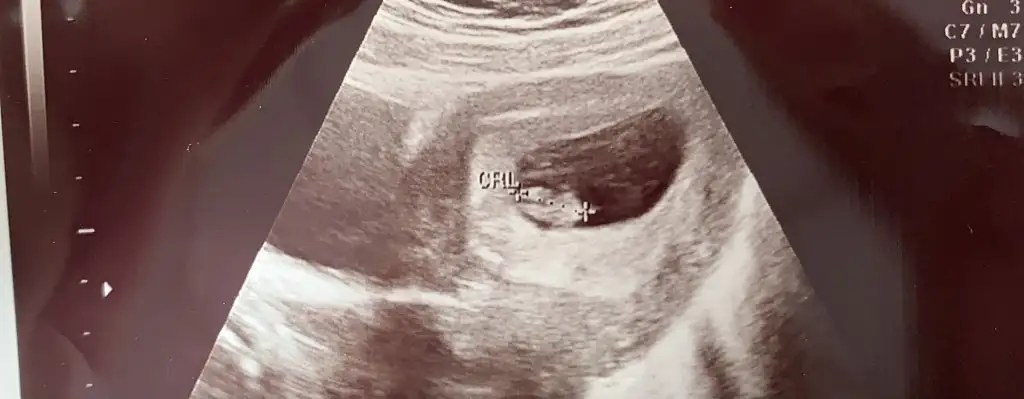

Kiz sankiEki Görüntüle 2777702 Eki Görüntüle 2777703 Eki Görüntüle 2777704 6+4 7+4 11+4 yorumlayabilir misiniz? Henüz belli olmadı cinsiyetimiz

bence kız sağ tarfta plasentaEki Görüntüle 2780164 Eki Görüntüle 2780165 merhabalar bir tahmin de ben isteyeyim 9+3 ve 7+² ye ait fotoğraflar her ikisi de karından usg

Erkek sankiEki Görüntüle 2780164 Eki Görüntüle 2780165 merhabalar bir tahmin de ben isteyeyim 9+3 ve 7+² ye ait fotoğraflar her ikisi de karından usg